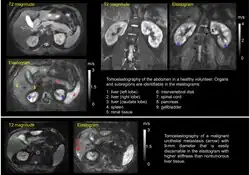

Tomoelastography requires external driver systems, which can efficiently generate shear waves throughout the entire field of view including tissues deep within the body. Multiple drivers can be combined such that waves propagate from the surface into the body from different directions to enable full illumination of larger regions with shear waves. Tomoelastography often employs mechanical vibrations at several driving frequencies for multifrequency wave analysis in order to stabilize inverse problem solutions for viscoelasticity reconstructions. A standard way of multifrequency viscoelasticity reconstruction is based on phase gradient analysis of plane waves[5] whereas other methods employ solutions of the Helmholtz equation.[6][7][8] The feasibility of tomoelastography was first demonstrated in the human abdomen using multifrequency MRE, where it was possible for the first time to display stiffness values (quantified as shear wave speed in m/s) across the entire axial MRI slice.[5] Although the elastograms are quantitative maps, tomoelastography images, like other radiological images, are often presented in standard gray-scale which gives more perceptual contrast to the subtle nuances than the color-scale.